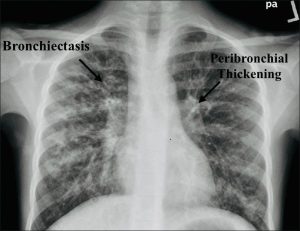

Chest X-ray:

Revealed hyperinflated lungs, diffuse peribronchial thickening, and predominantly upper-lobe bronchiectasis

Figure 1: Anteroposterior chest X-ray: Classic changes of cystic fibrosis, with hyperinflated lungs, diffuse peribronchial thickening, and predominantly upper lobe bronchiectasis. https://doi.org/10.4103/jopp.jopp_2_24